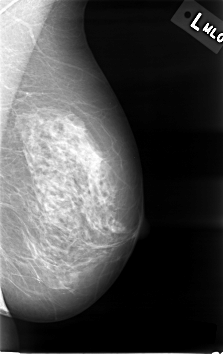

C_0001_1.LEFT_MLO

LEFT_MLO LINES 4592 PIXELS_PER_LINE 2896 BITS_PER_PIXEL 12 RESOLUTION 50 NON_OVERLAY